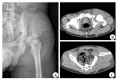

术前髋关节X线及CT检查 Preoperative radiographs and CT scan of the hip joint. A: Preoperative radiographs show a roof column acetabular fracture; B-C: CT scan reveals an acetabular fracture with roof wall and roof column.